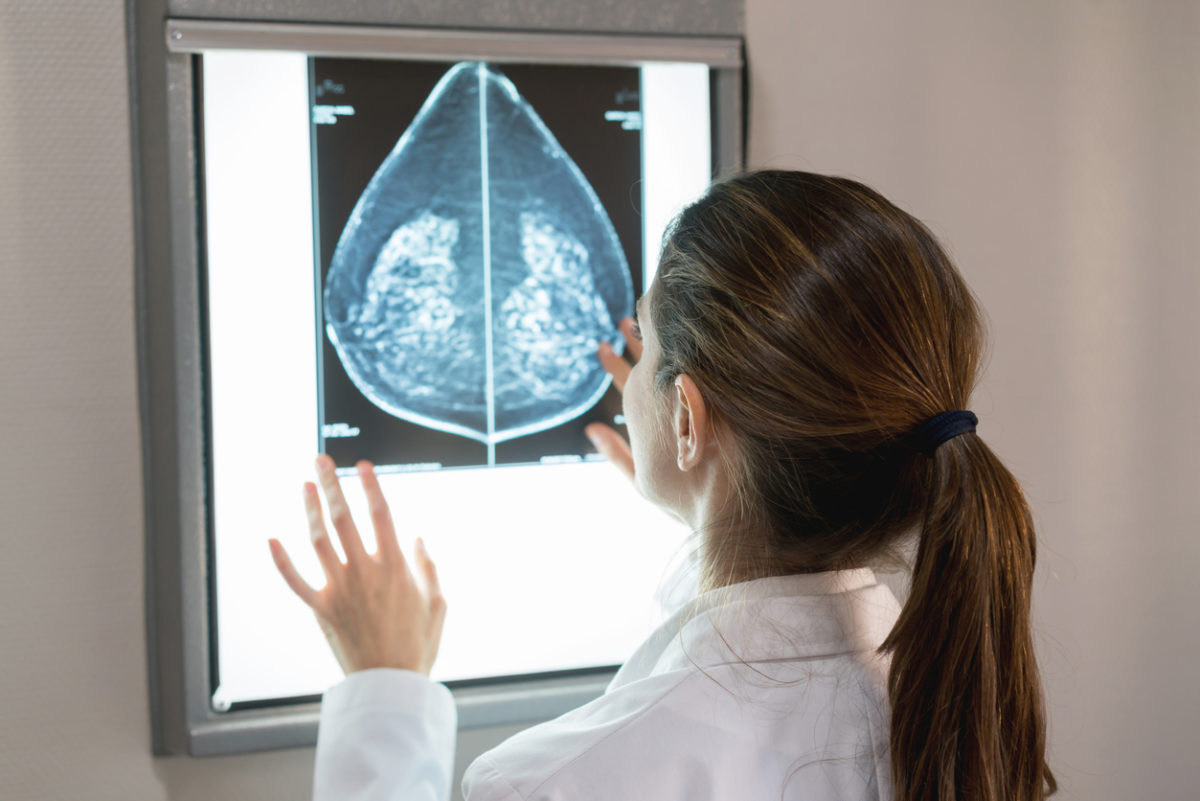

Εκ πρώτης όψεως η νέα έρευνα έρχεται σε σύγκρουση με τη διαδεδομένη αντίληψη ότι η γέννηση παιδιού προστατεύει από καρκίνο του μαστού. Οι ερευνητές διευκρίνισαν ότι αυτό ισχύει μεν, αλλά γίνεται αισθητό μόνο όταν έχουν περάσει τουλάχιστον δύο δεκαετίες από τη γέννα. Περίπου τα μισά περιστατικά καρκίνου του μαστού διαγιγνώσκονται σε γυναίκες έως 62 ετών.